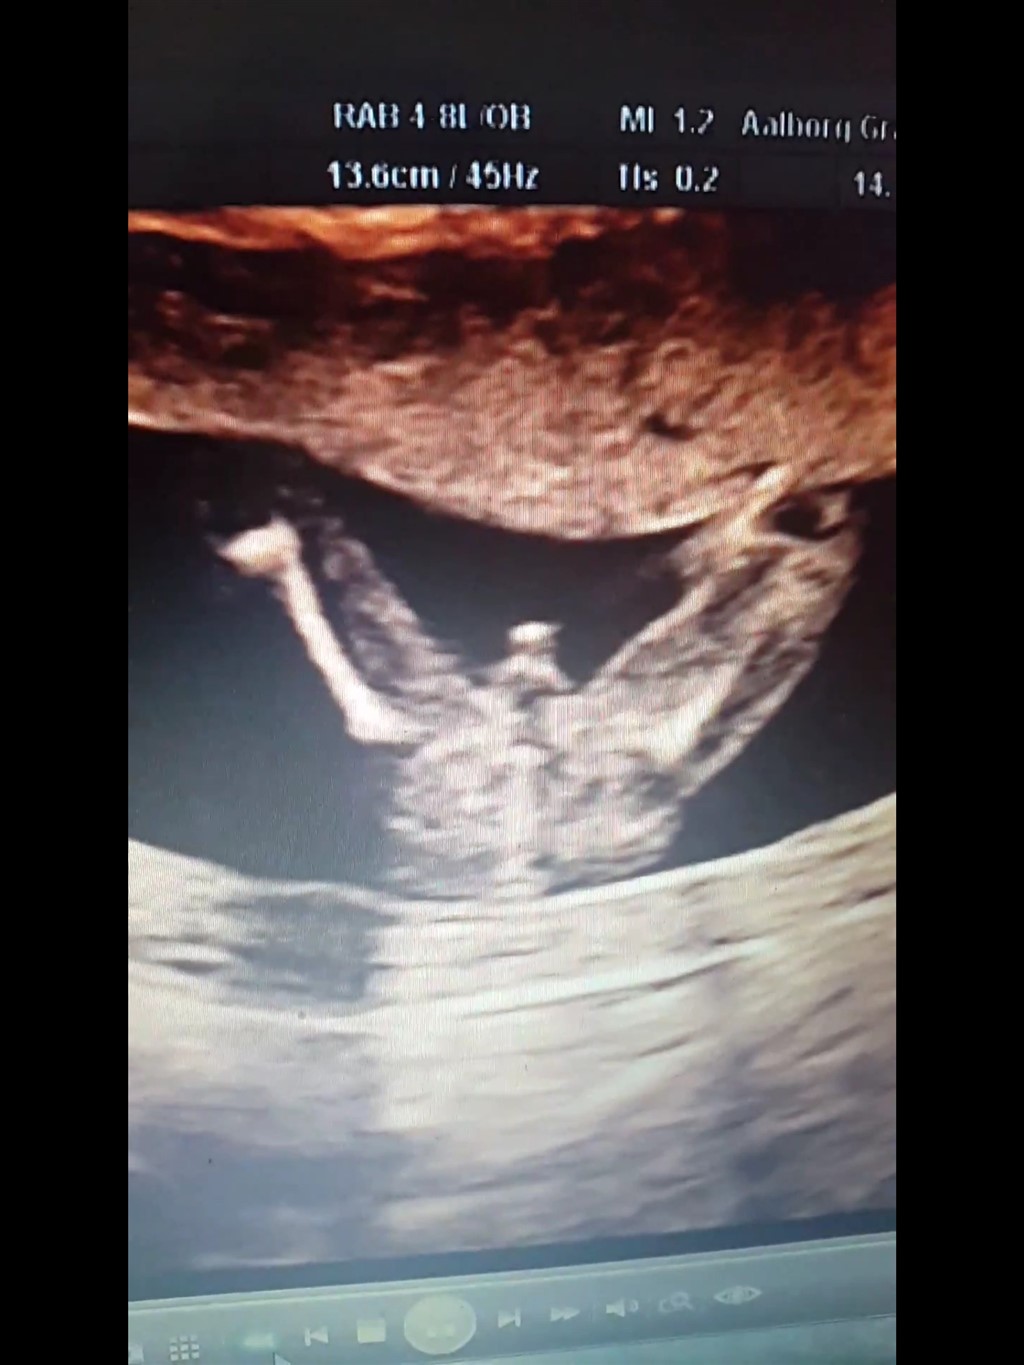

Jeg er ked af, at du ikke føler, du kan bruge vores tanker til noget. Men selv med en 3D er der ingen garantier. Jeg kender en, der fik sig en overraskelse med et 3D scannet barn. For de havde ikke kunne scanne barnet mellem benene 100procent.